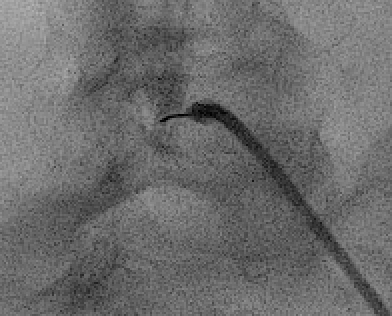

The "Scotty dog" view on oblique fluoroscopy — pedicle is the eye, transverse process the nose, superior articular process the ear, inferior articular process the foreleg. Needle target is the "6 o'clock" position of the pedicle (eye).

Oblique fluoroscopy to visualize "Scotty dog" at target level — pedicle is the eye; transverse process the nose; superior articular process the ear; inferior articular process the foreleg.

Needle target: "6 o'clock" position of the pedicle (safe triangle) — inferolateral to the pedicle and above the exiting nerve root.

Advance 22 G or 25 G spinal needle toward the target under oblique guidance; rotate to AP and lateral to confirm depth (needle tip at mid-pedicle depth on lateral).